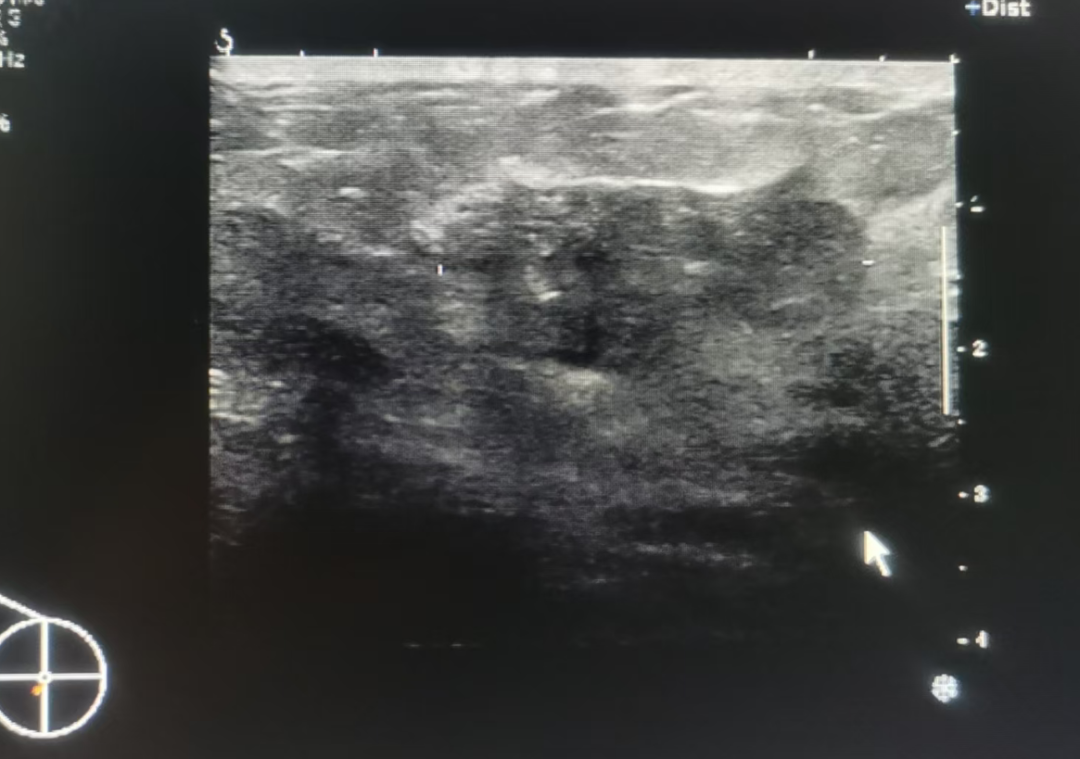

超聲示意圖:顯示一個形態(tài)不規(guī)則、邊界不清的混合回聲區(qū),內(nèi)部有漂浮的點狀回聲,后方回聲增強(qiáng)

乳腺膿腫形成:如果炎癥沒有得到控制,大量白細(xì)胞、細(xì)菌和壞死組織會聚集在一起,形成一包膿液,這就是膿腫。

■ 典型形態(tài):超聲下膿腫通常表現(xiàn)為一個不規(guī)則形或類圓形的“無回聲 ”或“混合回聲”區(qū)。

■ 無回聲:意味著內(nèi)部是液態(tài)的膿液,看起來像一塊黑色的、結(jié)構(gòu)單純的區(qū)域。

■ 混合回聲:意味著膿液黏稠或含有壞死組織碎片,看起來黑白相間,不均勻。

■ “厚壁”表現(xiàn):膿腫的邊界通常不清晰,周圍有一圈較厚的壁,這是因為機(jī)體正在試圖包裹和局限這些感染物。

■ 后方回聲增強(qiáng):在膿腫的后方,超聲波穿透液體后信號會增強(qiáng),出現(xiàn)一條亮帶,這是判斷內(nèi)部為液體的重要特征。